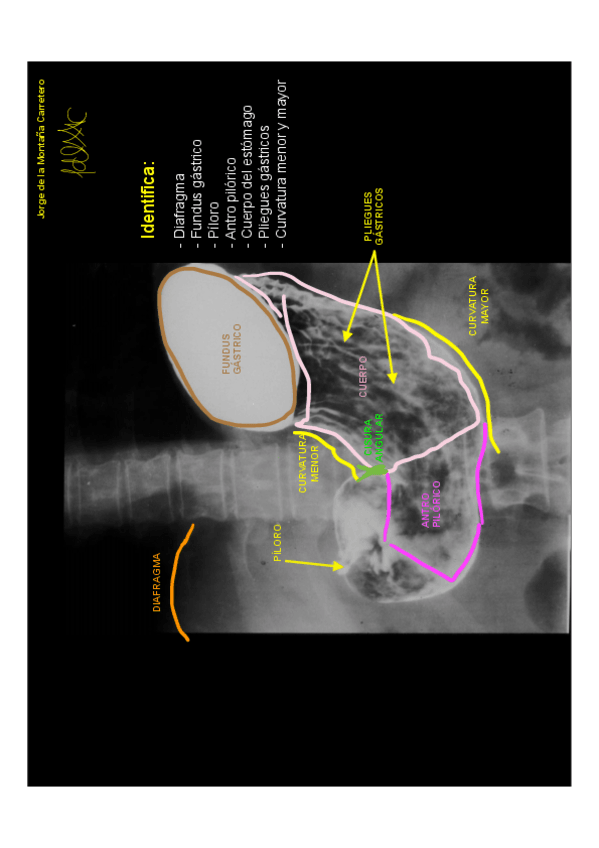

He publicado nuevos practicas de 1º Anatomía I: tronco y esplacnología: ANATOMÍA RADIOLÓGICA.pdf

14 páginas